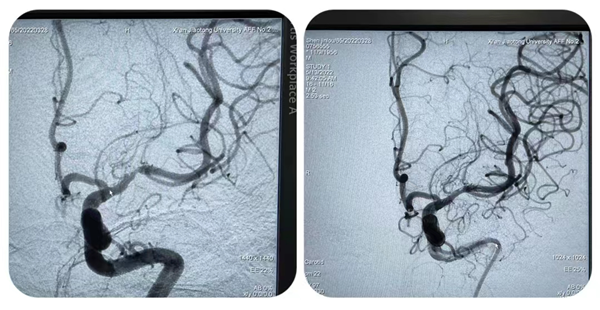

手术展播中,一例急诊取栓患者打破了原本的日程安排。一例50岁男性患者突发言语不利伴左侧肢体无力6小时入院,我院脑卒中绿色通道紧急启动,张桂莲主任紧急联系会务组,更改直播进程,对该例急诊手术进行了全国直播,手术由张茹副主任团队实施,最终手术实现了“一把通”,从患者入院至手术再通(包含急诊评估、住院流程办理、多模影像学检查等)仅耗时67分钟。急诊手术因其多种不确定性从来不是直播的常客,特别是在全国手术直播中更是极为罕见,科室打破常规思维,勇于挑战,衔接有序的卒中绿道、快速有序的手术过程、良好的手术效果令广大专家教授及介入同道纷纷称赞,为全国卒中中心及卒中绿色同道的建设展示了一个优秀的团队标杆。

图片2_副本.png

图片3_副本.png